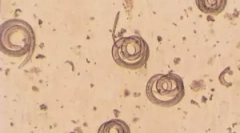

Ascaris Lumbricoides lub ludzkie askaris, odnosi się do okrągłych nicieni i mogą tylko mieszkać w ludzkim ciele. Inni przedstawiciele tego gatunku są charakterystyczne dla niektórych zwierząt. Mężczyźni dorosłych ludzkich askaridy mogą osiągnąć 25 cm długości, a kobiety rosną do 40. Okrągłe i blado różowe robaki o grubości około 0,5 cm są w stanie zamieszkać w organizmie człowieka do 2 lat. Naskórka (specyficzna powłoka wielowarstwowa) obejmuje ciało helminth, chroniąc go przed skutkami płynów sekretorycznych. Paszytanie w jelicie cienkim, Askarida nie jest przymocowana do jego ścian, ponieważ nie ma specjalnych urządzeń.

Stały ruch w kierunku przeciwieństwem do strumieniach żywności pozwala Askaraid, który odbędzie się w jelicie, dzięki czemu tylko martwe osoby i żeńskie jaja produkowane z masami koła. Nawożenie występuje w środkach seksualnych, a jego wdrożenie wymaga od osób obu płci. W krajach tropikalnych około połowy populacji jest zainfekowany tym rodzajem robaków, ale także w umiarkowanej łożysku klimatycznej jest dość powszechnym zjawiskiem. Dorosła kobieta jest w stanie odtworzyć dzień około jednej czwartej miliona jaj, które wychodzą z zakażonego organizmu na zewnątrz z kałami i może być utrzymywany w glebie przez kilka lat, czekając na ich szansę na korzystanie z cyklu życia.

Askariusze